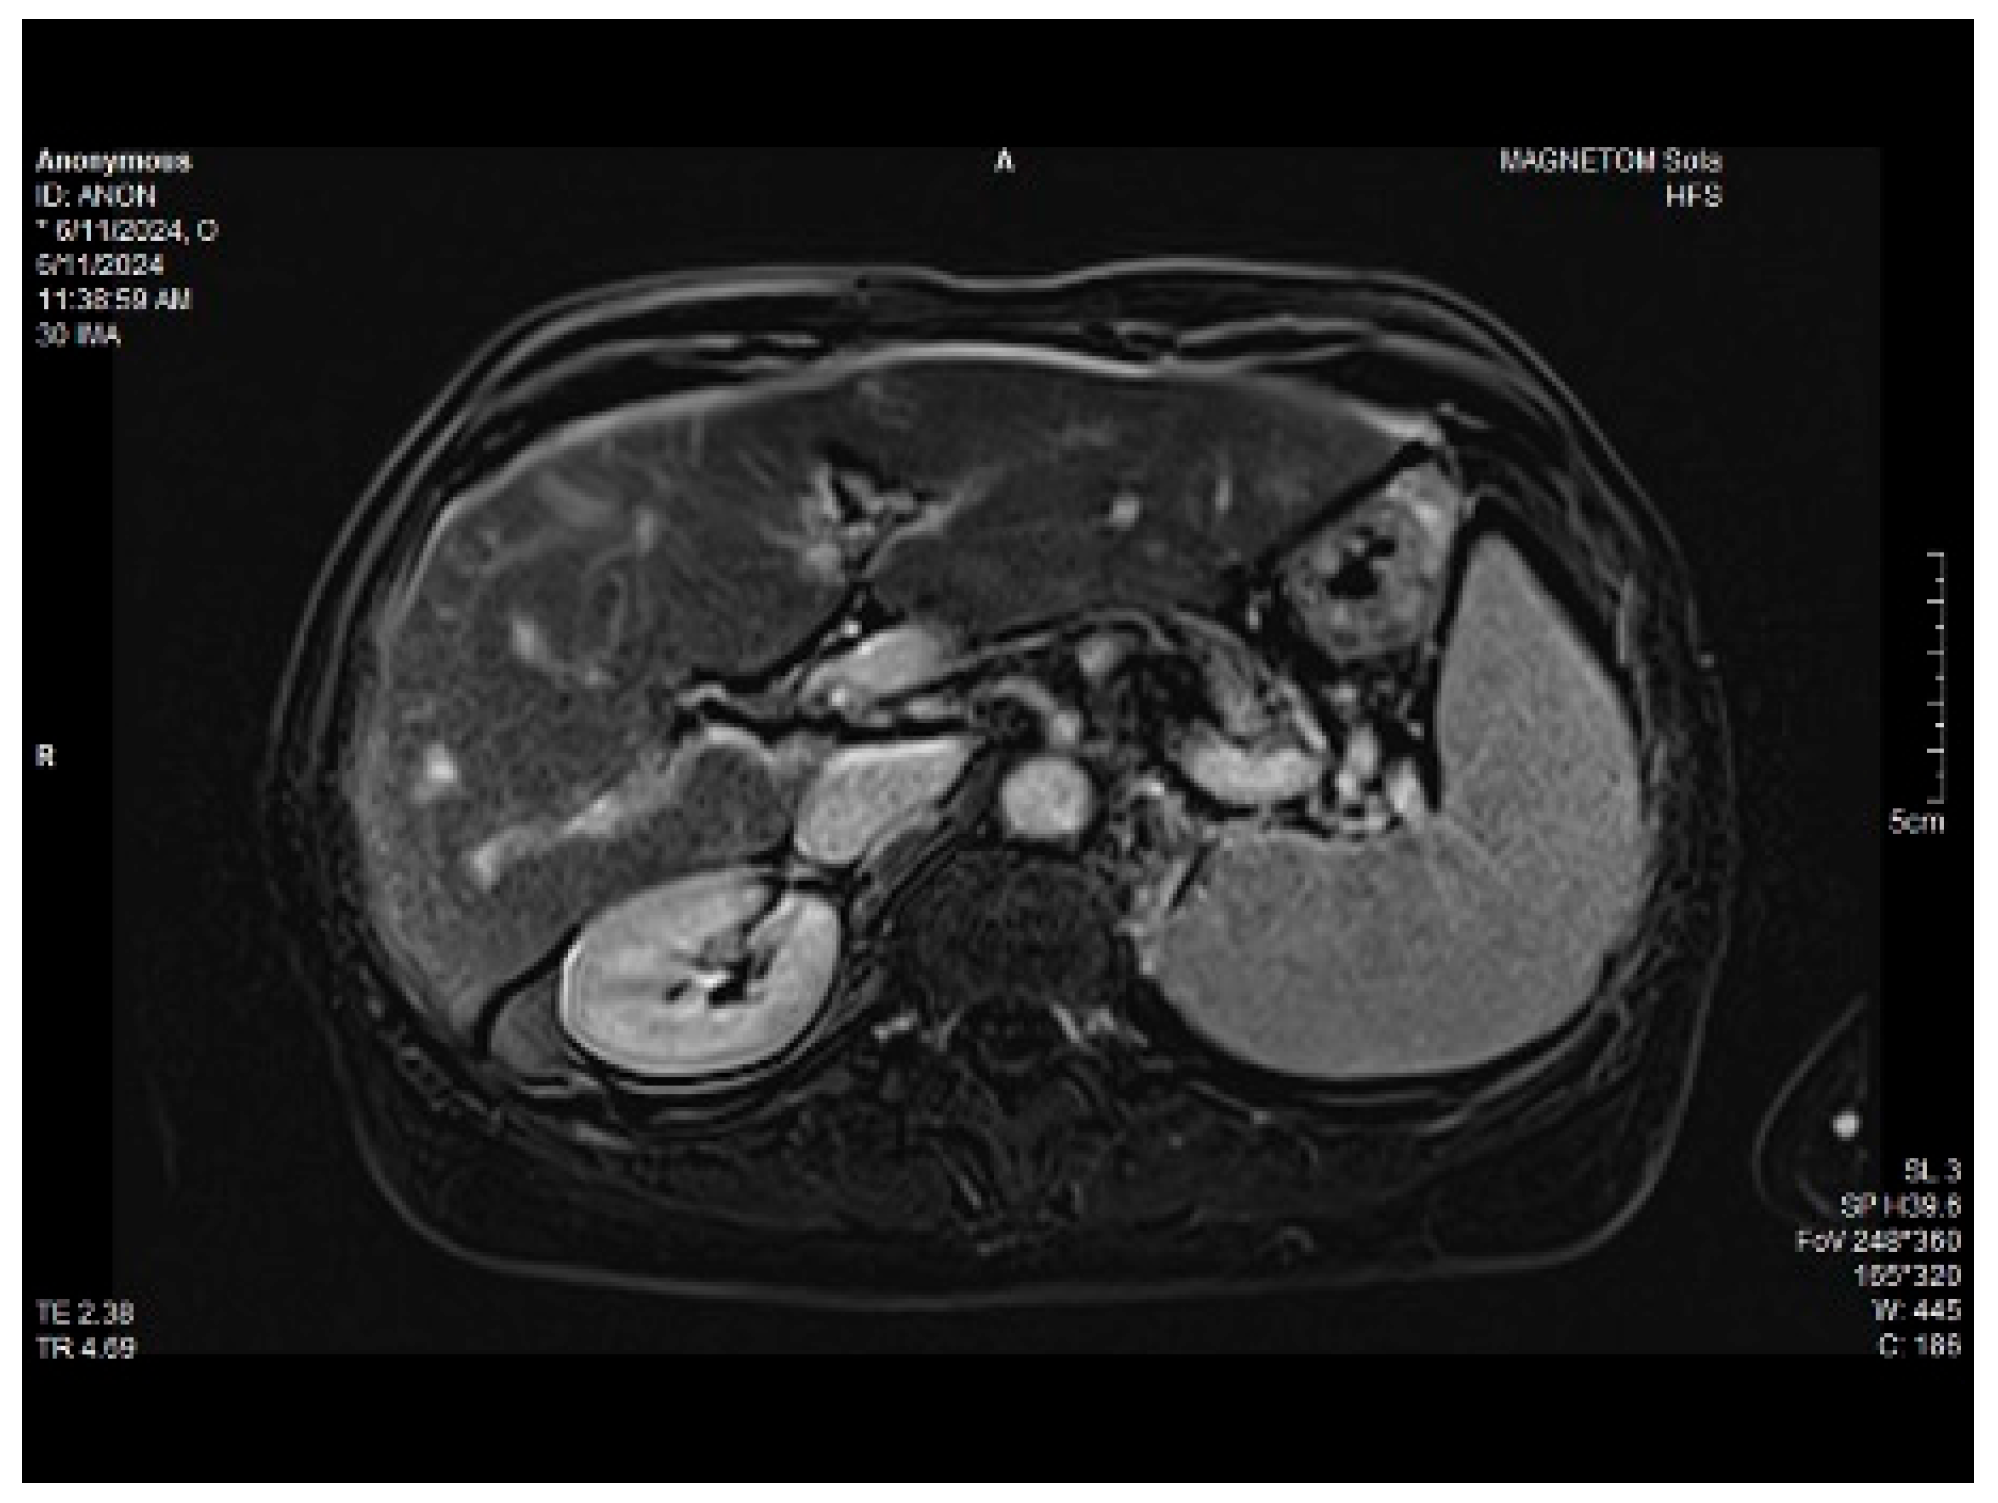

Abdominal MRI study confirmed the hepato-splenomegaly, ascites and the patency of the portal vein system. In addition, small veno-portal shunts were highlighted at the periphery of both hepatic lobes. Various MRI features are depicted in Figure 6, Figure 7, Figure 8 and Figure 9.

Figure 8. Massive thickening of the gallbladder wall, MRI features.